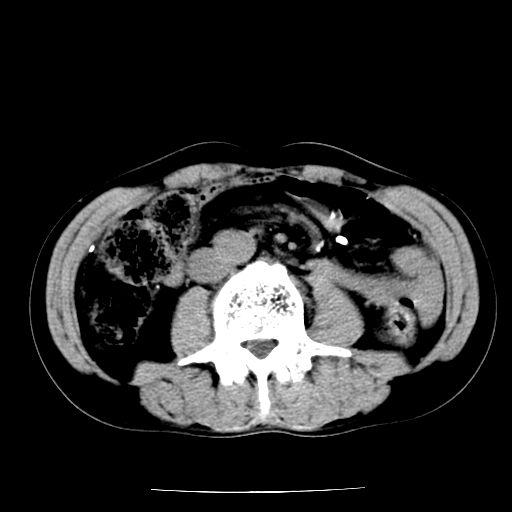

男,59岁,“结核性胸膜炎”30余年,胸部经常疼痛,多次x检查提示“肺部”炎症。腹部疼痛5日,b超提示:“肝内短管结石,余显示不清,建议进一步检查。”

两肺结核并右侧胸腔积液;脾脏、腹腔及腹膜后淋巴结结核[陈旧性];肝内胆管结石

胸部腹部都是结核(双肺。纵隔淋巴结,肝脏,脾脏,肠系膜)